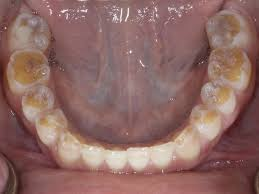

The Connection Between Celiac Disease and Dental Enamel Defects helps identify gluten issues early. Learn how malabsorption affects your child’s…